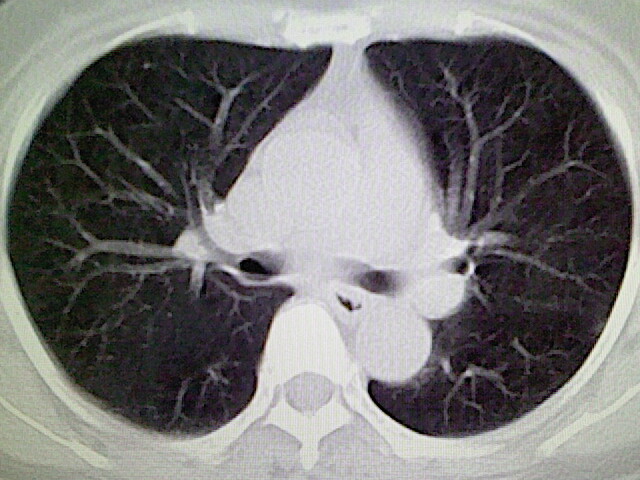

女,52岁,咳嗽,咳痰多日

左下肺陈旧纤维索条!

左肺舌段炎性改变

我见过几例,为炎症后纤维条索

慢性炎症后改变

考虑慢性炎性病灶粘连牵拉改变。

左肺舌叶纤维锁条病变。

左肺上叶下舌段炎症并局部胸膜反应。

左肺舌叶纤维索条影。

左肺舌叶段陈旧性病变

左肺舌段炎性反应。片子的质量太不好了。

左肺舌段炎性

炎性改变

左肺舌叶纤维索条影